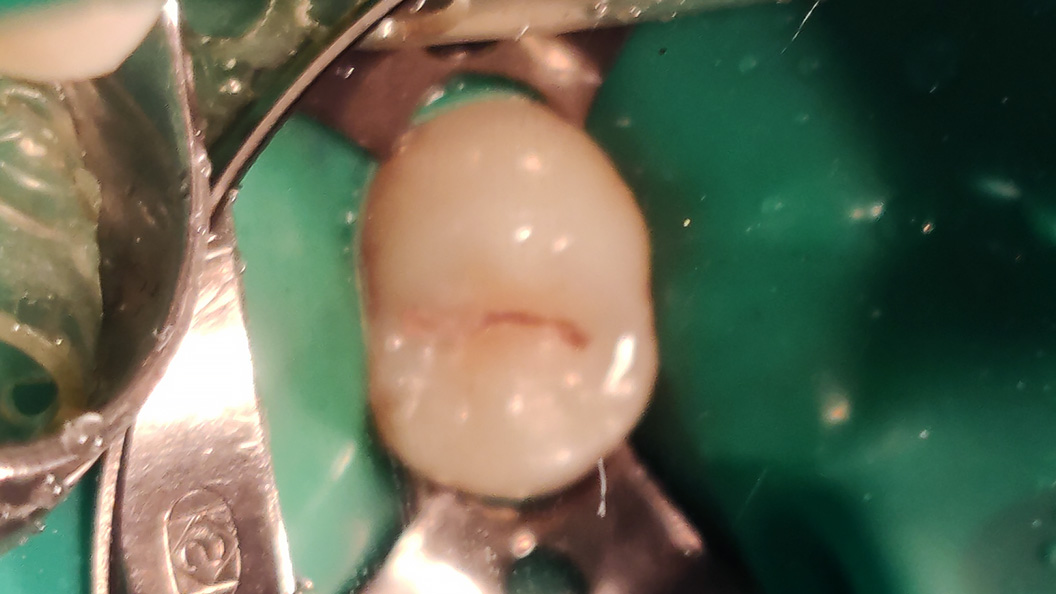

До и после лечения

Пациент обратился с жалобами на эстетический недостаток в области правого верхнего зуба. После обработки полости под контролем кариес-маркера была обнаружена полость средней глубины. Дно и стенки плотные, гладкие, при зондировании крепетируют. Реакция не перкуссию и холодную пробу отрицательная. Диагноз — хронический средний кариес.

- наложение системы коффердам

- механическая обработка кариозной полости

- медикаментозная обработка полости раствором хлоргексидина 2%

- наложение пломбы Estelite Sigma Quick (OA3+A2)

- микроконтурирование и макроконтурирование пломбы